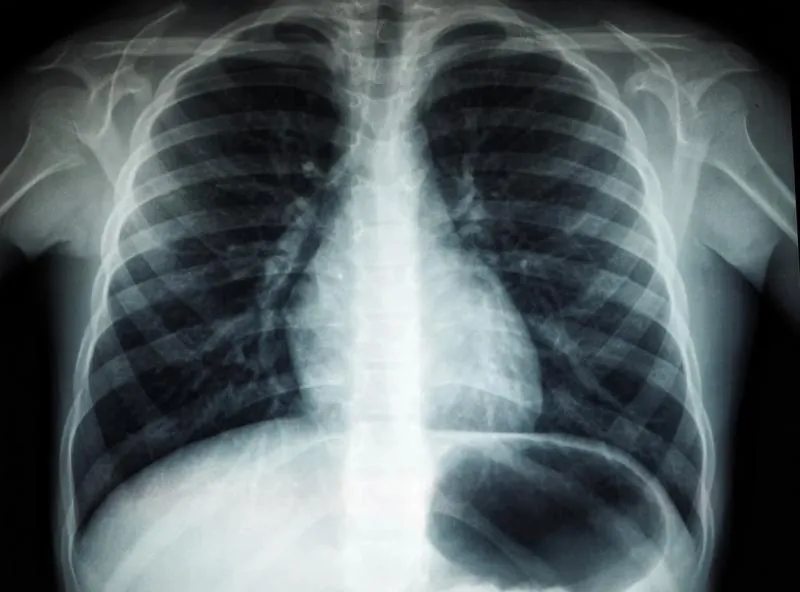

Минздрав: ранняя диагностика и скрининг - самая эффективная профилактика рака легких

Минздрав: ранняя диагностика и скрининг - самая эффективная профилактика рака легких Фото: unsplash